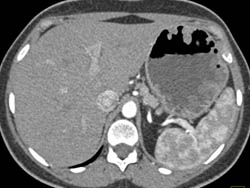

Antral Carcinoma